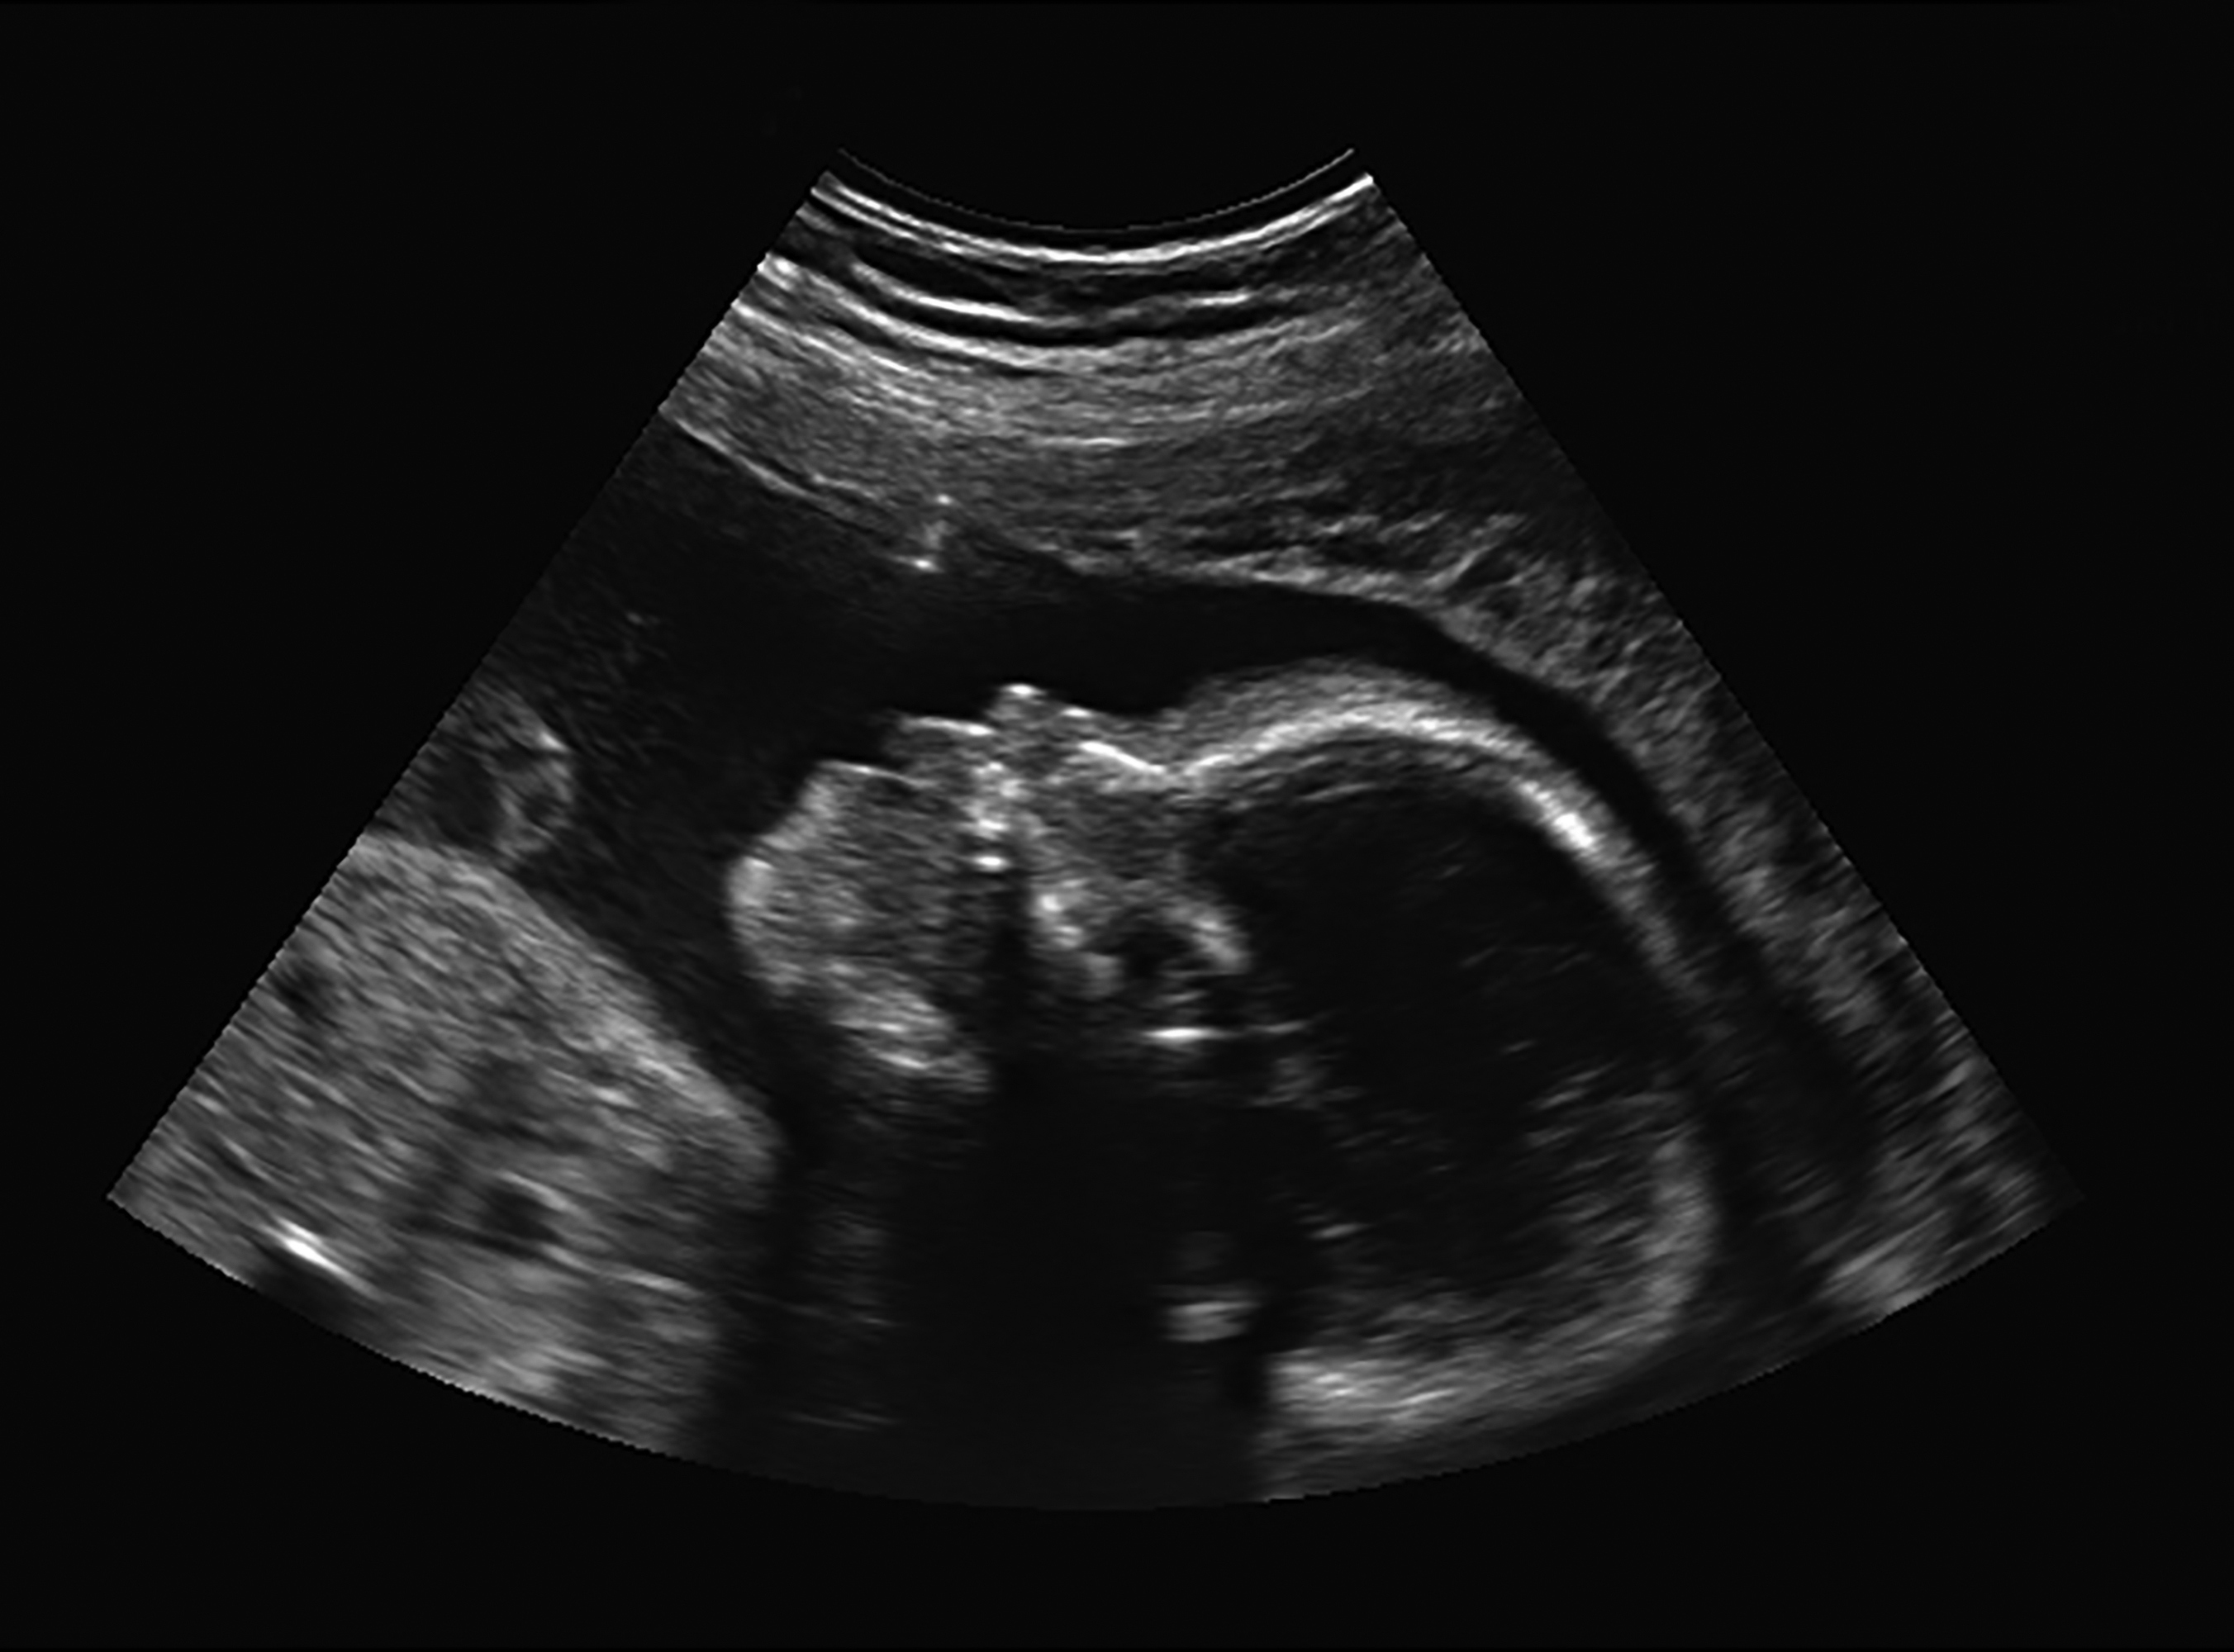

Canadian couple Romeo Crisostomo and Romeila Son learned at their 20-week ultrasound that their unborn baby had myelomeningocele, a form of spina bifida that occurs when the spinal column doesn’t close properly during the fetus’ development.

In June, medical staff from Mount Sinai applied general anesthetic to Son and anesthetized the 25-week-old fetus using a needle inserted through the mother’s abdomen. Incisions were made into the uterus to offer access to the fetus, and the spinal defect was covered with skin. Amniotic fluid that was drained from the uterus during the procedure was replaced using a catheter, ensuring that the fetus would remain healthy during the final weeks of pregnancy.